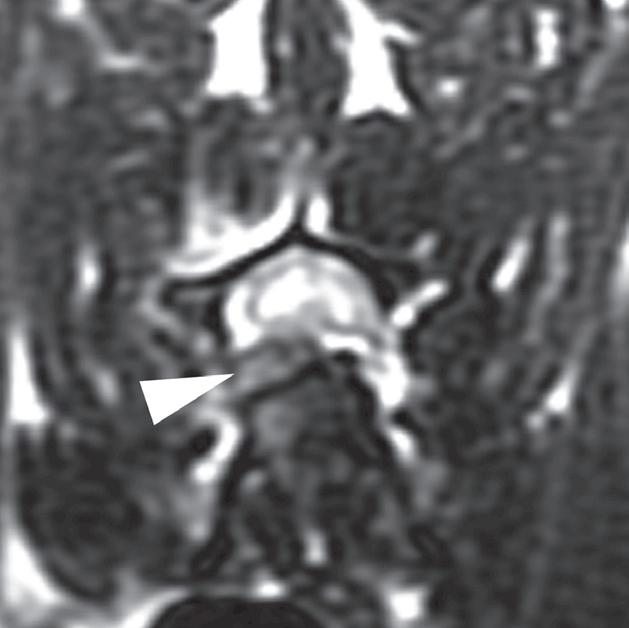

Rycina

3.2.8. Podwichnięcie kręgów szyjnych ze złamaniem wyrostka stawowego (pies) TK i MR

Badania wykonano u 5-letniej samicy mieszańca w typie teriera, która została pogryziona w okolicy szyjnej przez większego psa tego samego dnia, w którym wykonano badania. Podczas wizyty u psa zaobserwowano deficyty neurologiczne z neuroanatomiczną lokalizacją w obrębie C6–T2. Radiogramy przeglądowe ukazały grzbietowe podwichnięcie kręgu C7 względem C6 oraz zwężenie przestrzeni międzykręgowej C6–C7 (a – grot strzałki). Podobne zmiany uwidoczniono na obrazach TK w projekcji strzałkowej i 3D (b, f – grot strzałki). Dodatkowo stwierdzono wieloodłamowe złamanie z przemieszczeniem prawego doczaszkowego wyrostka stawowego kręgu C7 (c–e – strzałka). Dla porównania przedstawiono prawidłowy lewy wyrostek stawowy (f – strzałka). W badaniu MR przestrzeń międzykręgowa C6–C7 była zwężona i wykazywała obniżoną intensywność sygnału w obrazach T2-zależnych (i – strzałka), a przemieszczony materiał dyskowy znajdował się w prawej dobrzusznej części kanału kręgowego (g, h – grot strzałki). W obrazach występują cechy ucisku na rdzeń kręgowy (g–i) oraz zwiększona intensywność sygnału w sekwencji T2-zależnej w obrębie rdzenia na poziomie C6–C7 (h, i), co wskazuje na jego uszkodzenie wewnętrzne. Materiał dyskowy został chirurgicznie usunięty z kanału kręgowego, a podwichnięcie zredukowano i ustabilizowano operacyjnie